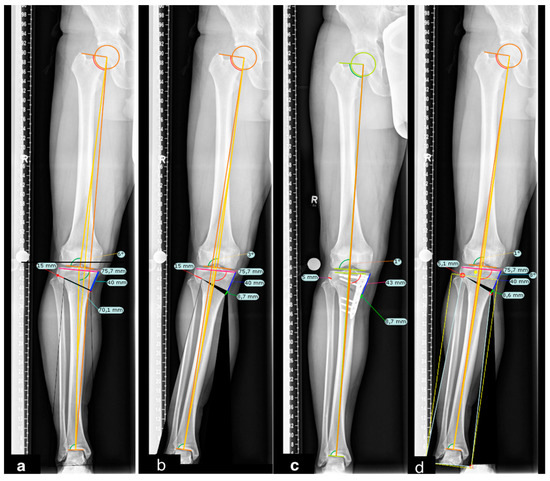

Influence of Medial Osteotomy Height and Hinge Position in Open Wedge High Tibial Osteotomy: A Simulation Study

2. Materials and Methods

2.1. Radiographic Assessment